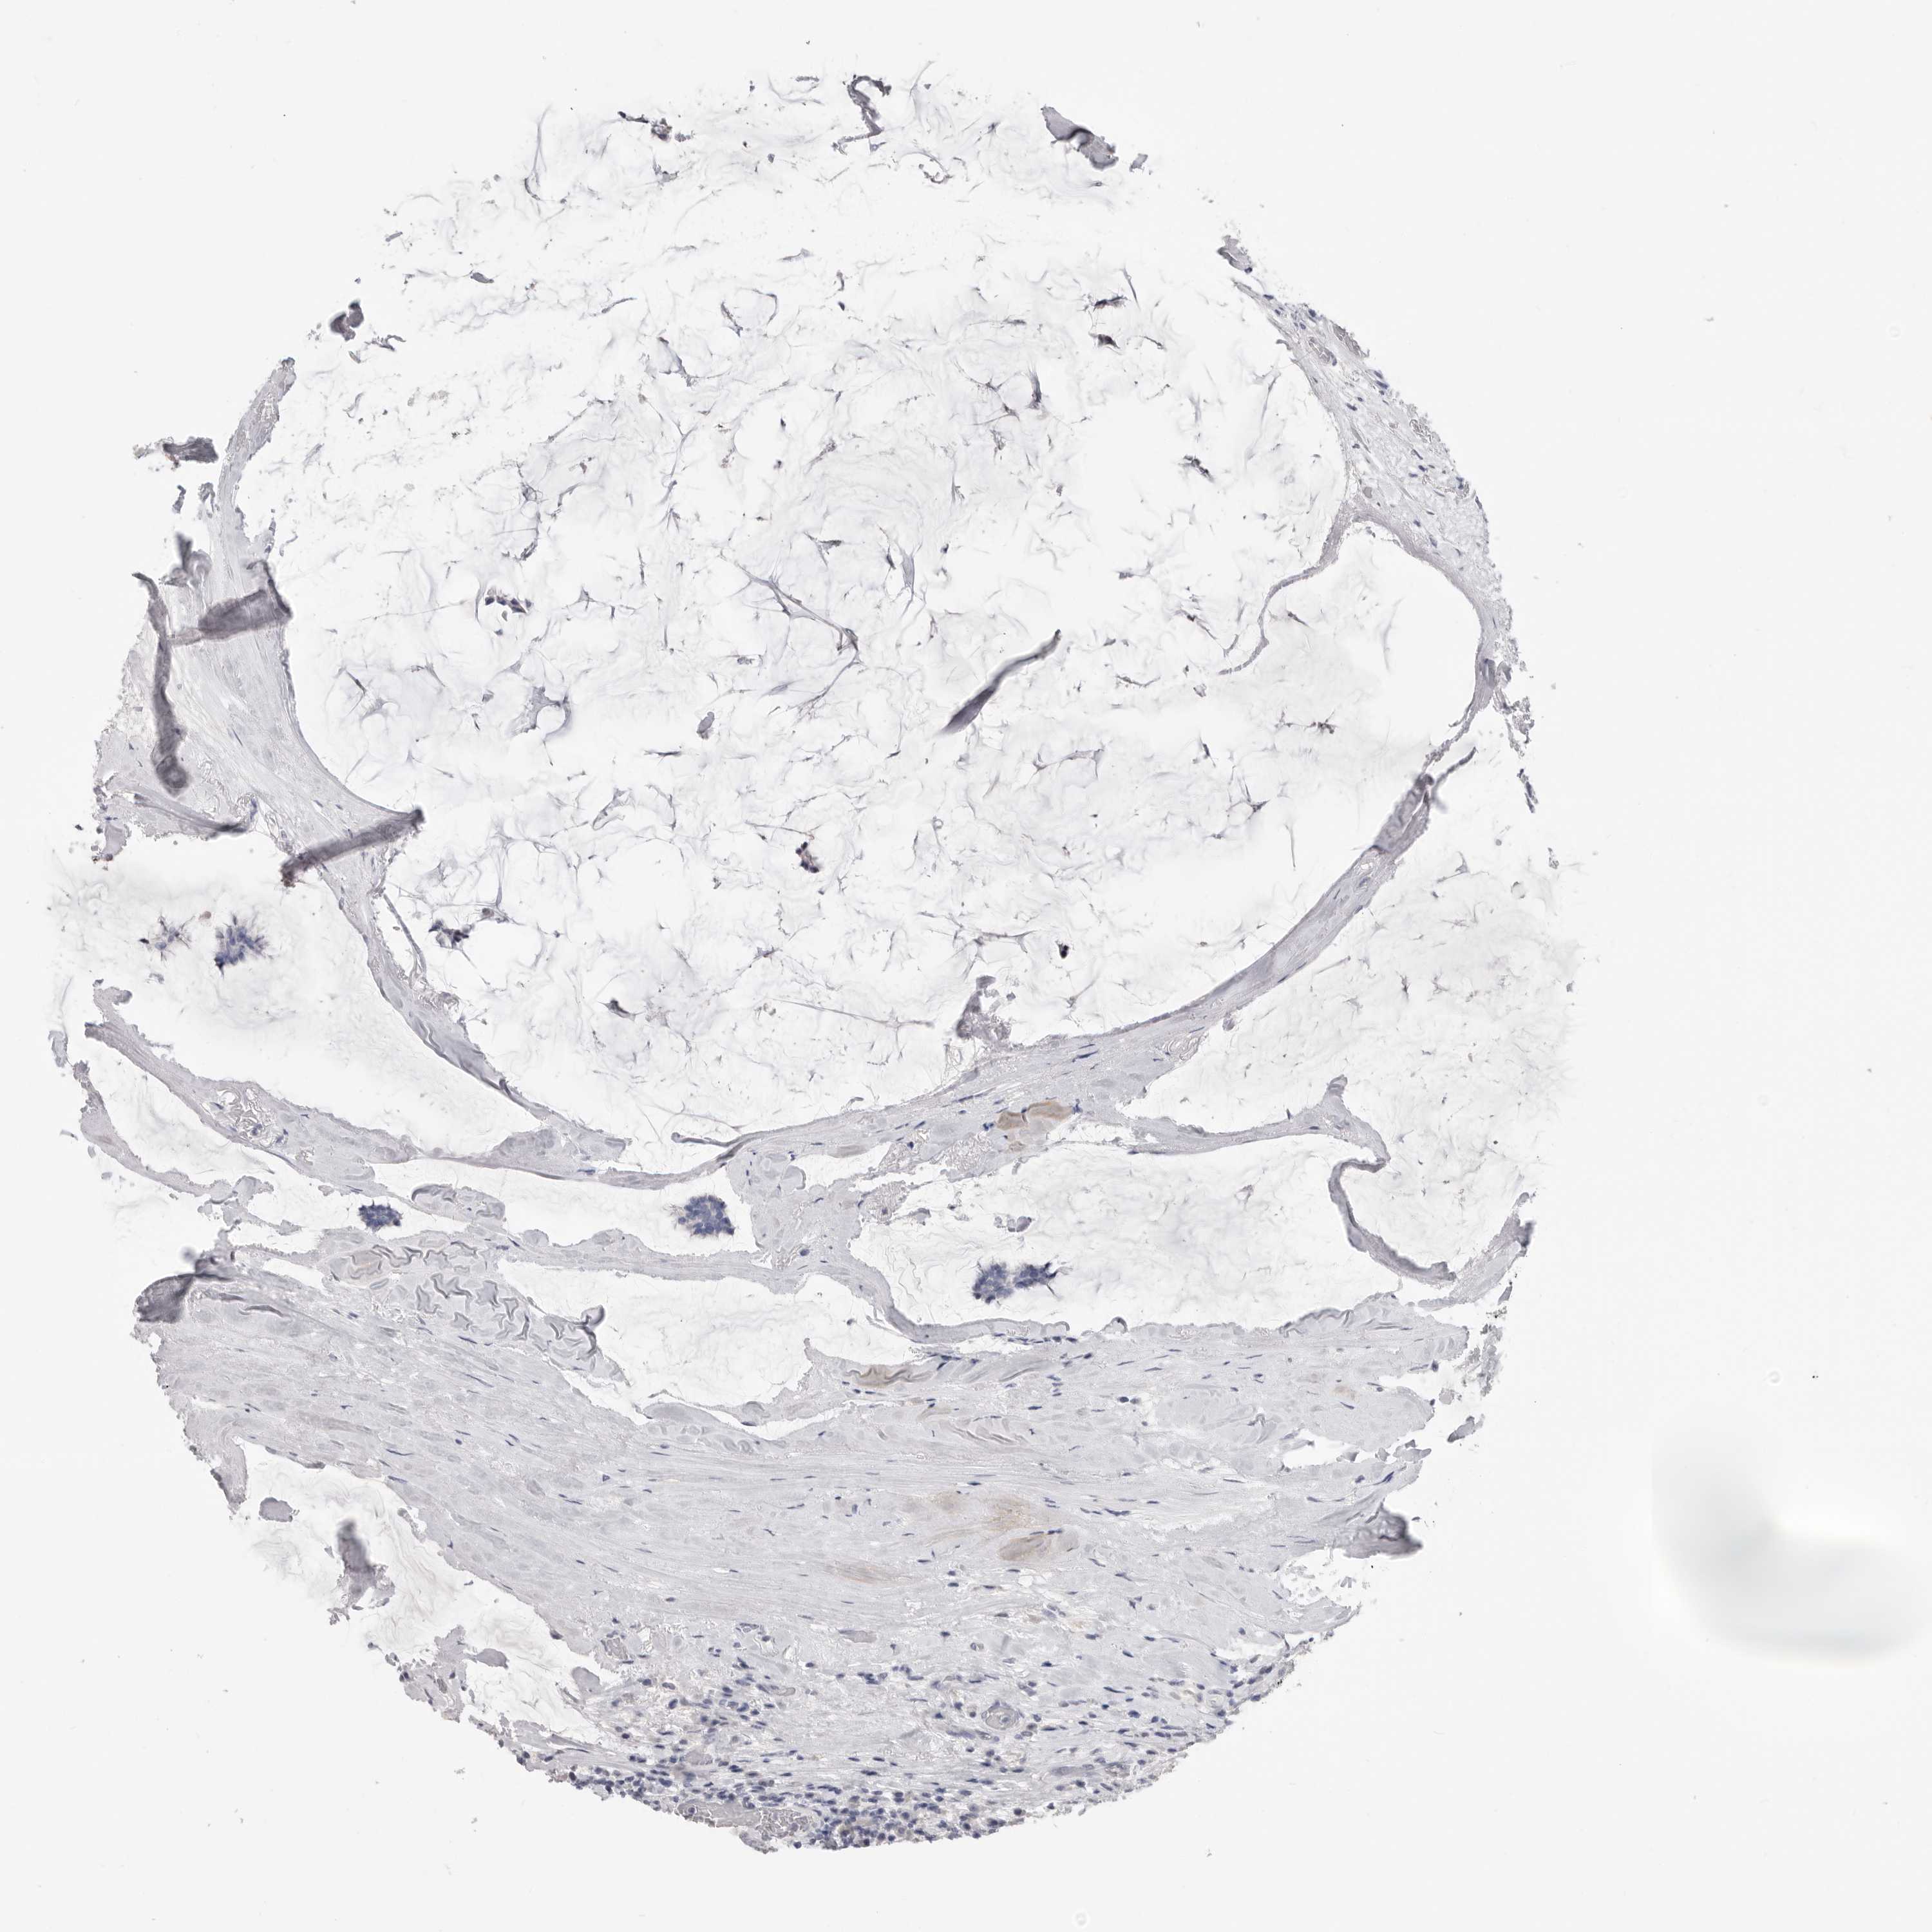

BRCA TCGA BRCA VALIDATION PROTEIN EXPRESSION

Breast cancer

Human cancer